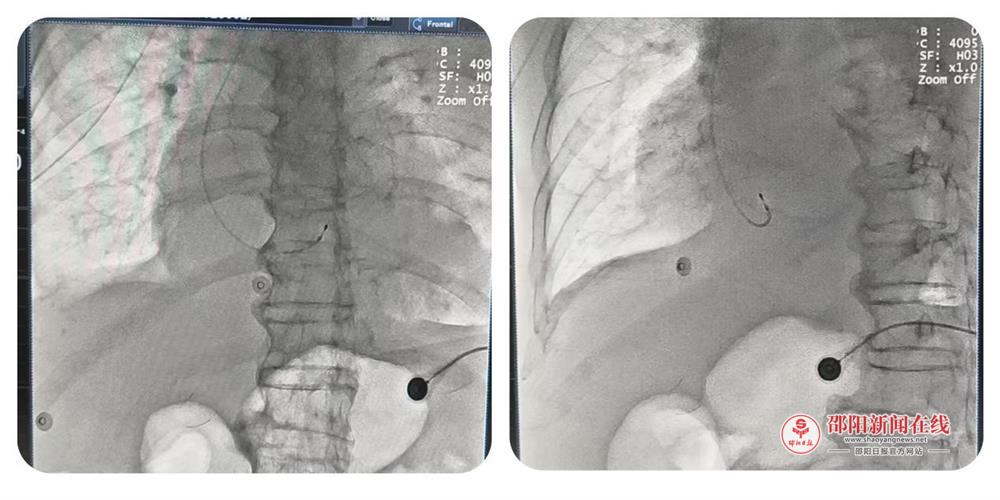

时间就是生命!面对这场突如其来的生命考验,呙旭明主任当机立断,决定迎难而上,在ICU病房内为患者进行紧急床旁手术。在呙主任的精准指挥下,重症医学科团队紧密协作,凭借娴熟的技术与丰富的经验,在床旁顺利完成了心脏起搏电极导线的置入与起搏系统的调试工作。整个操作过程顺利,术后即刻可见成效——患者心率迅速恢复稳定,血流动力学指标随之得到显著改善,为后续的综合治疗赢得了宝贵的“时间窗”与稳定的生命基础。

此次床旁临时心脏起搏器的成功植入,不仅是一次技术上的突破,更是该院多学科协作应对急危重症能力的集中体现。它有效解决了危重患者无法转运至介入导管室进行手术的临床难题,为该院处理同类复杂危重病例积累了宝贵经验,也展现了邵东市中医医院重症医学科团队敢于担当、技术过硬的专业风采。